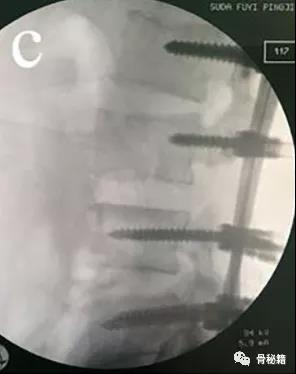

前后移位

对于前后移位就相对复杂一些1、解锁脊柱的关节面

如果坎墩严重,需要先植入椎弓根螺钉,咬除部分后方椎板,进行后柱的撑开。

先植入能植入的椎弓根螺钉, 深度过椎弓根即可

先进行短阶段的撑开,撑开之后暴露关键的前移的椎体再植入椎弓根螺钉进行二次撑开

要点:进行初次撑开之后,取下一侧的棒,植入关键椎体的椎弓根螺钉再换另外一侧,同法。

撑开时,可先用直棒,最后复位好了后再进行棒的塑性恢复腰椎前凸来达到较好的稳定

最后添加横联和植骨融合来增加稳定性